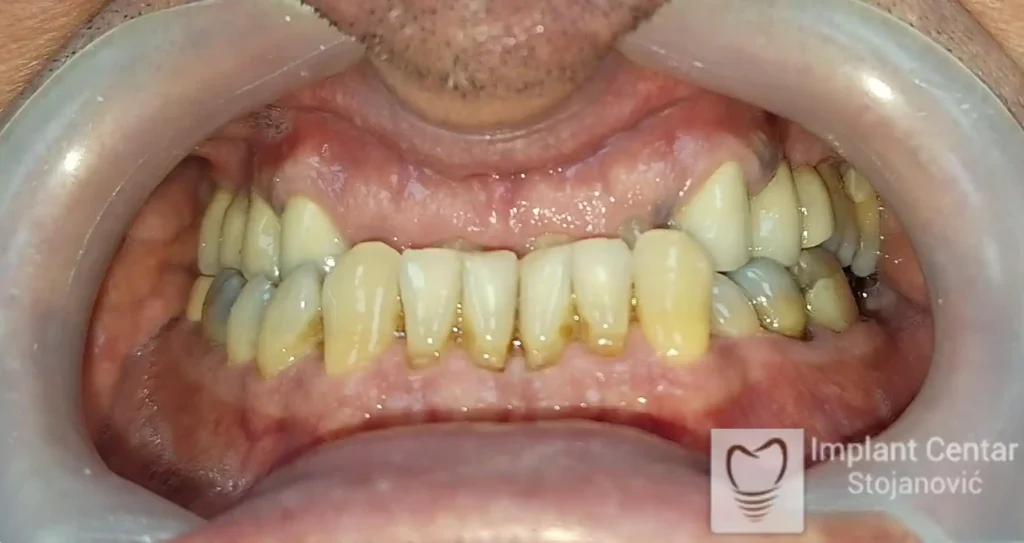

Na slici 1. i slici 2. prikazan je izgled pacijenta pre početka terapije – klinički i rendgenološki.

Na slikama 1 i 2 prikazan je klinički izgled pacijenta pre početka terapije. Nakon detaljnog kliničkog pregleda, analize radioloških snimaka, kao i razgovora sa pacijentom o njegovim željama i očekivanjima, izrađen je sveobuhvatan plan terapije. Terapija je podrazumevala vađenje preostalih zuba, ugradnju dentalnih implantata i izradu fiksnog protetskog rada na implantatima.